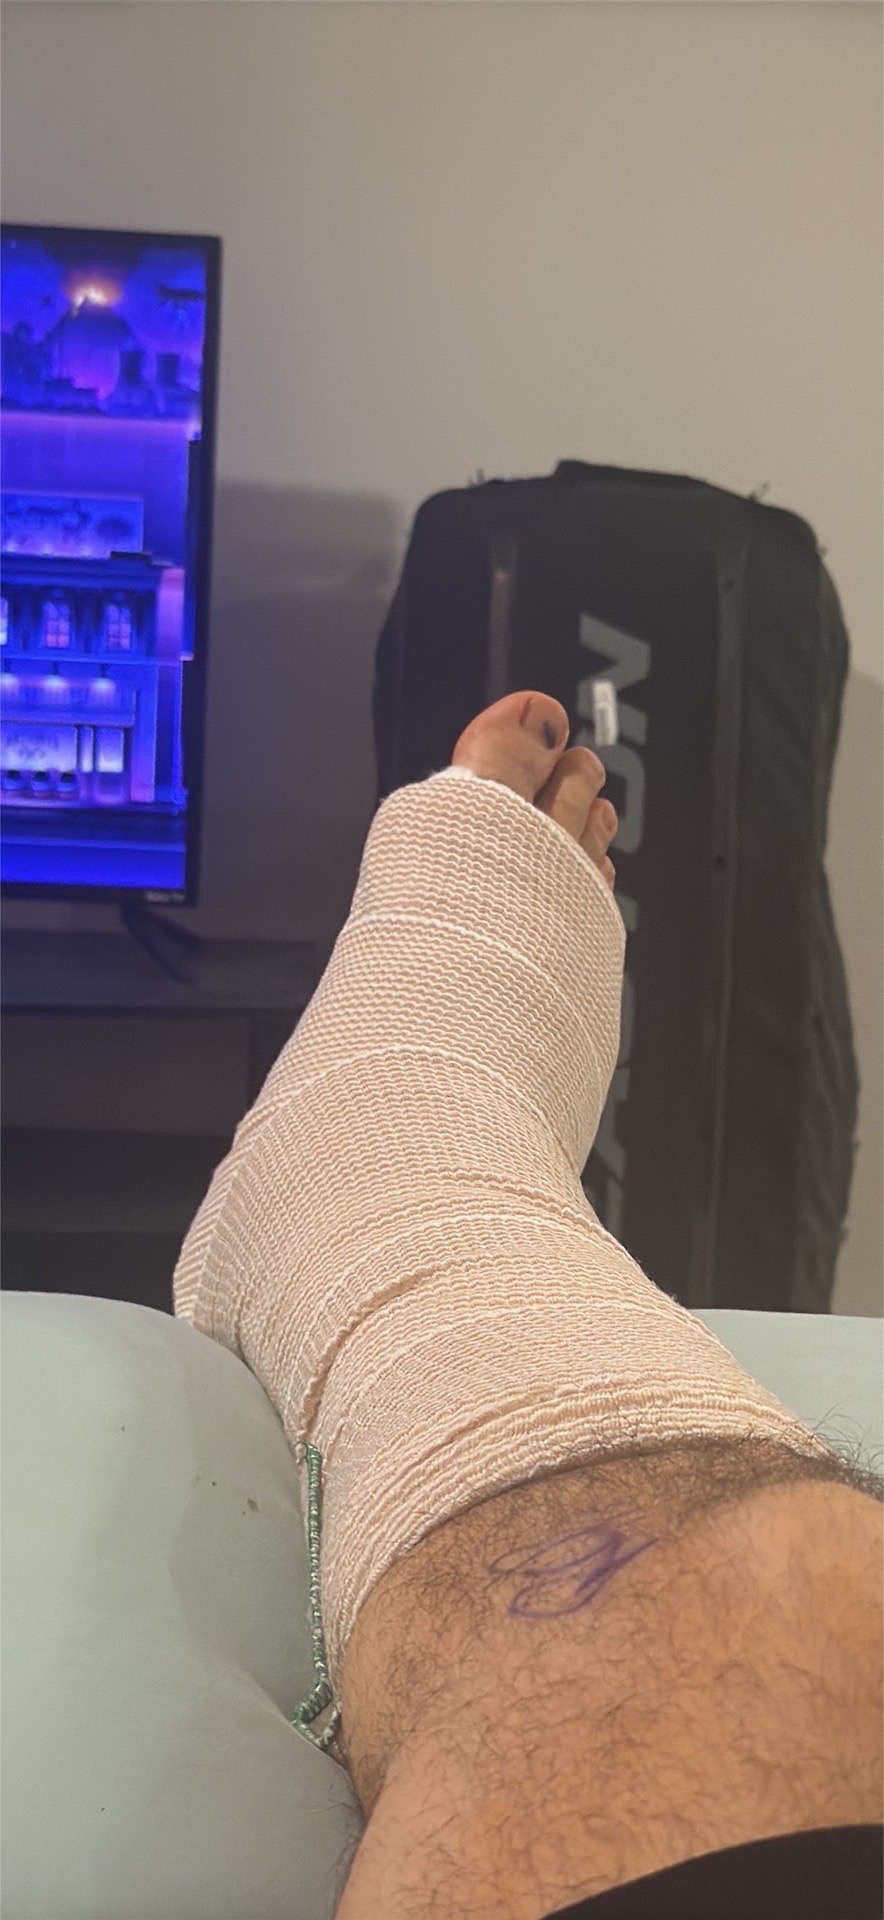

Recently, during a bull riding event, I suffered a serious accident that resulted in a broken ankle. I had to undergo surgery, and now I am in recovery. Unfortunately, this injury has left me unable to work for the time being, which has been very difficult because I have always depended on my own hard work to support myself.

Recentemente, durante uma competição de montaria em touros, sofri um grave acidente que resultou em uma fratura no tornozelo. Tive que passar por uma cirurgia e agora estou me recuperando. Infelizmente, essa lesão me deixou impossibilitado de trabalhar por enquanto, o que tem sido muito difícil, pois sempre dependi do meu próprio trabalho para me sustentar.